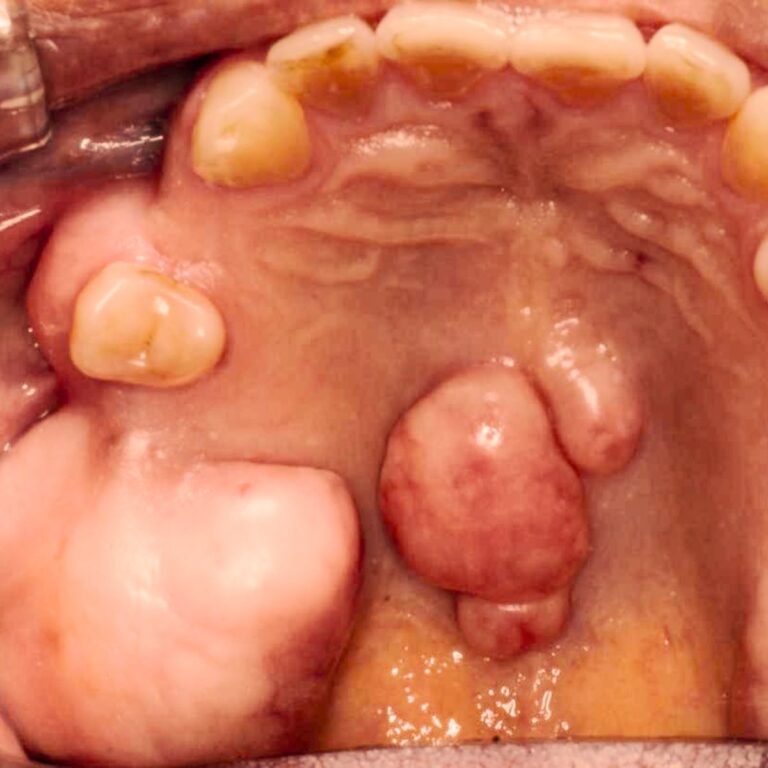

- Bultos, quistes o crecimientos en encías o mucosa

¿Cuándo evaluar una lesión en la boca?

Algunas alteraciones en la mucosa oral pueden parecer leves, pero requieren control profesional para descartar complicaciones.

Se evalúa cuando existe:

- Lesiones que no cicatrizan en 10–15 días

- Bultos, quistes o crecimientos en encías, labios o mejillas.

- Mucoseles (bolitas con contenido líquido).

- Cambios de color (blanco, rojo o oscuro) en la mucosa.

- Zonas endurecidas, dolorosas o que sangran.

- Irritaciones persistentes o molestias sin causa clara

Ante cualquier cambio en tu boca, lo más importante es evaluarlo a tiempo.

La detección temprana mejora significativamente el pronóstico.

Realizamos diagnóstico clínico y, si es necesario, estudios complementarios para definir el tratamiento adecuado

¿Cuándo debo preocuparme por una lesión o bulto en la boca?